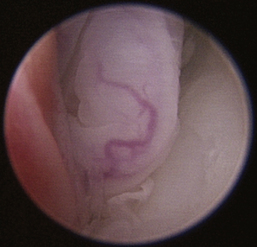

Normal turbinates have a smooth, pink-to-white surface and a spatial alignment that provides channels for the passage of air. The color varies and appears tan in the caudal nasal cavity. Turbinates come in different shapes and sizes, but the surface should be smooth. Ethmoid turbinates in the caudal nasal cavity will have a characteristic stippled or corrugated appearance (Figures 19-13 through 19-16). Ulcerations or various proliferations of the mucosa are indicative of disease. These changes are typically diffuse and accompanied by a lot of mucus. Mucus can be thin to purulent. Copious amounts can be flushed out of the nasal cavity to allow better visibility. The specific disease is determined by biopsy. After full examination of the nasal cavity, run the scope along the floor of the nasal sinus to the level of the choanae. Keeping the scope pointed in a ventral medial direction prevents inadvertent trauma or penetration of the cribriform plate. The index finger of the free hand can be used to follow the scope as it moves caudally over the hard palate; the surgeon can then palpate the scope through the soft palate when it moves into the nasopharynx. Some force is needed to complete this procedure and may result in increased bleeding.

Figure 19-16 Normal canine ethmoid turbinate.

Flexible fiberoptic endoscopes are preferred and utilized effectively by some clinicians, but we do not routinely use them for primary evaluations. Retrograde placement of these scopes behind the soft palate allows visualization of the nasopharynx, choanae, and caudal segments of the nasal passages. Flexible endoscopes can also be used in an antegrade fashion through the nostrils in some patients but are limited by the scope and patient size. Irrigation is limited with small fiberoptic scopes; biopsy instruments are diminutive at best, and the reliability of representative tissue collection should be questioned when this technique is used. The 2.5-mm fiberscope has a single channel used for both irrigation and instrument passage. When an instrument is passed, the irrigation flow is markedly reduced, drastically affecting visualization during biopsy collection. The spatial orientation estimation and direct visualization provided by flexible endoscopes is inferior when compared with rigid telescopes. In most cases, rigid telescopes can be passed through the nasal cavity, choanae, and into the nasopharynx, eliminating the need for flexible retrograde rhinoscopy.